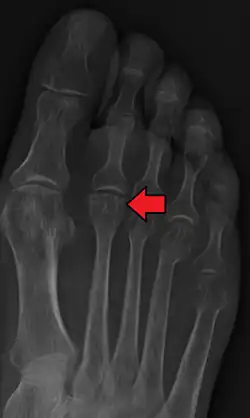

Freiberg disease as seen on plain film

2. Radiography: X-rays may reveal flattening, sclerosis, or fragmentation of the metatarsal head.

X-ray of Freiberg disease.jpg

The prognosis for Freiberg disease varies depending on the stage at diagnosis and the chosen treatment approach. Early diagnosis and appropriate management can lead to favorable outcomes, with many patients experiencing significant pain relief and improved function. However, some individuals may develop chronic pain or limitations in physical activities, particularly if the condition is left untreated or progresses to advanced stages.